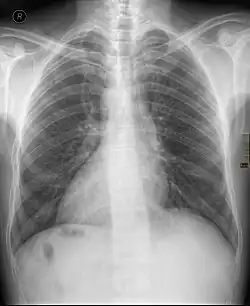

Chest X ray of a person with dextrocardia situs inversus showing the cardiac apex pointing towards right | |

Dextrocardia (from Latin dextro 'right hand side' and Greek kardia 'heart') is a rare congenital condition in which the apex of the heart is located on the right side of the body, rather than the more typical placement towards the left.[1] There are two main types of dextrocardia: dextrocardia of embryonic arrest (also known as isolated dextrocardia)[2] and dextrocardia situs inversus. Dextrocardia situs inversus is further divided.

Dextrocardia situs inversus refers to the heart being a mirror image situated on the right side. For all visceral organs to be mirrored, the correct term is dextrocardia situs inversus totalis.[5][6]